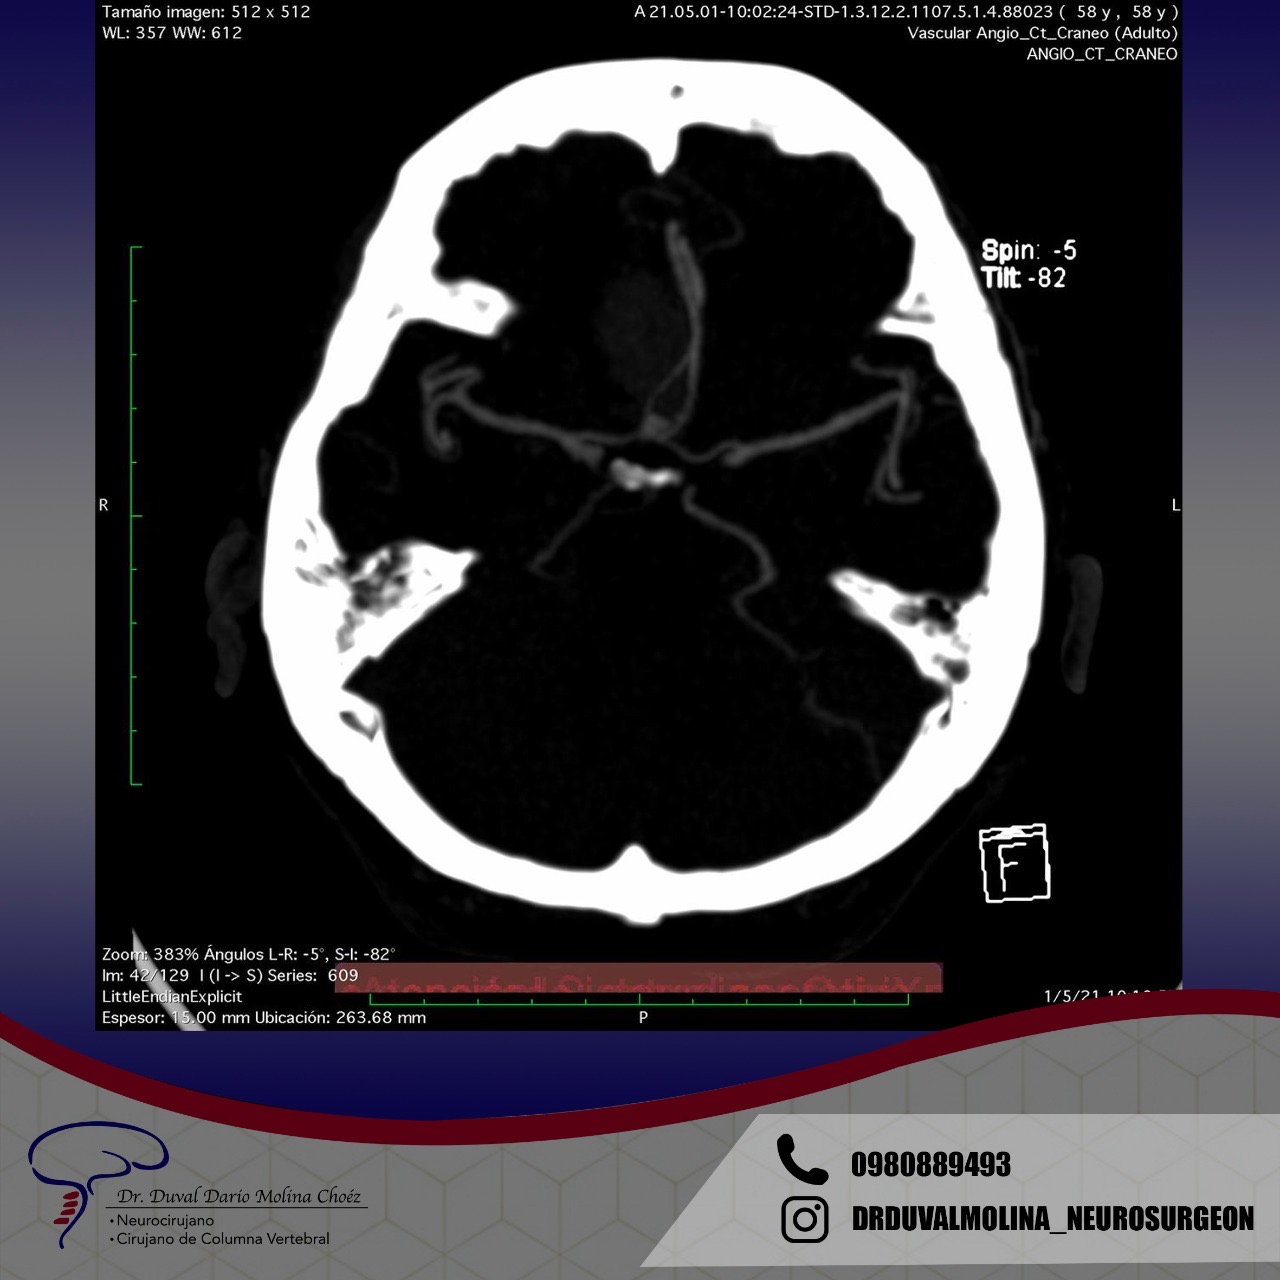

Los aneurismas son un abultamiento de una pared arterial que representa un punto débil. Se encuentran en alrededor del 2-3% de la población y suelen permanecer en silencio hasta que se rompen. Un aneurisma roto generalmente se presenta con el peor dolor de cabeza que haya existido y un inicio rápido de problemas neurológicos. El patrón característico de la hemorragia se denomina «hemorragia subaracnoidea».

También puede causar la muerte instantánea o provocar una discapacidad permanente. En algunos casos, hay un fuerte historial familiar o una condición genética. La afección hereditaria más común es la enfermedad renal poliquística del adulto. Los factores de riesgo para la ruptura del aneurisma incluyen el tabaquismo, la hipertensión mal controlada y el esfuerzo excesivo. Si no se trata, existe un riesgo anual acumulativo de ruptura y se recomienda una vigilancia periódica.

El patrón de hemorragia típico que se observa después de la ruptura de un aneurisma. La forma y la ubicación del aneurisma pueden predecir su comportamiento y también determinar qué opción de tratamiento es probable que sea la mejor. Alternativamente, si el aneurisma representa un bajo riesgo de ruptura o un alto riesgo quirúrgico, podemos optar por seguirlo con imágenes en serie. La intervención está diseñada para detener el flujo de sangre hacia el aneurisma, eliminando así el riesgo de hemorragia. Se puede realizar de forma endovascular rellenando el aneurisma desde dentro («coiling» endovascular), o mediante técnicas microquirúrgicas abiertas («clipaje»).

Se pueden usar varias modalidades de imagen para definir la MAV. La TC (Tomografía) y su variante Angiotomografía brindan información sobre la ubicación y la anatomía vascular estática, incluidos los vasos que irrigan y drenan la MAV. La resonancia magnética nos dice en qué parte del cerebro se encuentra la MAV y ayuda a medir el riesgo y los enfoques quirúrgicos y brinda información sobre hemorragias previas. La angiografía cerebral brinda información dinámica detallada sobre los patrones de flujo y el drenaje venoso. Es la prueba más sensible y poderosa, sin embargo, es técnicamente más «invasiva» y conlleva un riesgo muy pequeño de accidente cerebrovascular.